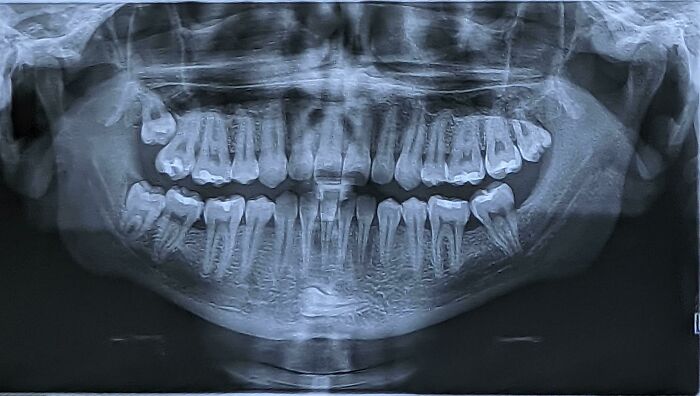

#2 V mojej brade mám zub